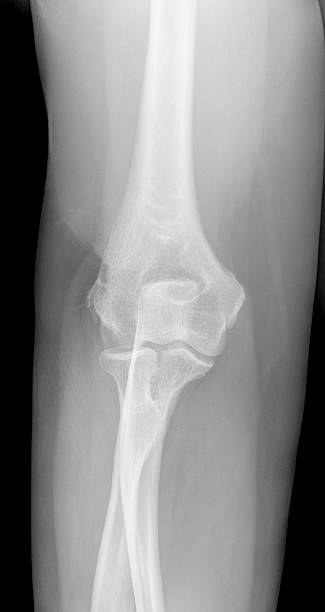

테니스엘보는 테니스엘보라는 이름에 걸맞게 테니스 백핸드 자세에서 팔꿈치 부위에 무리한 힘이 가해지면서 발생하는 팔꿈치 통증으로 정식 진단명은 외측 상과염으로 불립니다. 비단 이 통증은 테니스를 치는 사람에게만 나타나는 것이 아니라 전반적으로 팔을 많이 사용하는 분들에게 나타나며 관리가 잘 되지 않으면 만성질병으로 고착화 될 수 있습니다.

테니스엘보가 고착화 되는 경우 주요 통증 부위인 팔꿈치 바깥에서 통증이 시작하여 가동범위도 줄어들게 되어 팔을 돌리는 것 자체가 힘이 들게되고 덩달아 불편감을 느끼며 일상생활도 불편해지기 때문에 이번시간에는 테니스엘보 증상과 치료법에 대해 자세히 알아보겠습니다.

테니스엘보의 증상은 다양한 고통을 수반하는데 우선적으로 팔꿈치 외측에서 통증이 시작해 찌릿찌릿한 통증이 계속됩니다. 덩달아 팔에 힘이 빠지고 심한 경우 쉽게 떨어뜨리게 됩니다. 이러한 통증은 팔꿈치가 지속적으로 아프기 때문에 물건을 잡거나 드는 행위 자체에 고통을 느끼게 됩니다.